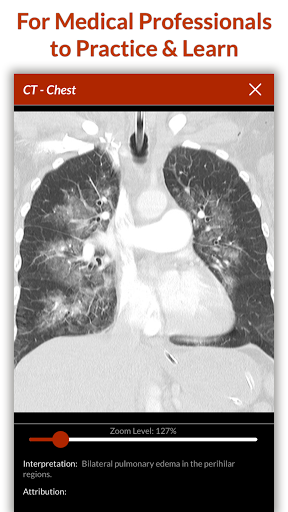

Full Code challenges you to take on complex clinical cases in a realistic 3D emergency room. Whether you are a medical student, resident, paramedic, nurse, PA or experienced physician you will enjoy the challenge of solving Full Code cases. Our library includes over 105 scenarios with a mix of common occurrences, trauma cases, pediatric patients, life-threatening illnesses and obscure diseases. We add 2 new scenarios each month and we frequently cover clinical hot-topics. Earn CME credit hours with realistic medical simulation.

Begin by taking a history and performing a physical exam, then click on equipment in the virtual resuscitation bay to order tests and perform interventions. Choose amongst a host of drugs, bedside tests, labs, and imaging to help you narrow the differential diagnosis. Our physiology engine will change the vitals based on your interventions and the patient’s condition just as they would in real life. While you zero in on the final diagnosis and definitively treat the patient you can consult with specialists and nursing staff for assistance, but the patient’s survival rests in your hands.

Full Code vous met au défi de prendre en charge des cas cliniques complexes dans une salle d'urgence 3D réaliste. Que vous soyez étudiant en médecine, résident, ambulancier, infirmier, AM ou médecin expérimenté, vous apprécierez le défi de résoudre des cas de code intégral. Notre bibliothèque comprend plus de 105 scénarios avec un mélange d'événements courants, de cas de traumatisme, de patients pédiatriques, de maladies potentiellement mortelles et de maladies obscures. Nous ajoutons 2 nouveaux scénarios chaque mois et nous couvrons fréquemment des sujets d'actualité cliniques. Gagnez des heures de crédit CME avec une simulation médicale réaliste.

Commencez par prendre un historique et effectuez un examen physique, puis cliquez sur l'équipement dans la baie de réanimation virtuelle pour commander des tests et effectuer des interventions. Choisissez parmi une multitude de médicaments, de tests de chevet, de laboratoires et d'imagerie pour vous aider à affiner le diagnostic différentiel. Notre moteur de physiologie changera les signes vitaux en fonction de vos interventions et de l’état du patient, comme ils le feraient dans la vraie vie. Pendant que vous vous concentrez sur le diagnostic final et que vous traitez définitivement le patient, vous pouvez consulter des spécialistes et du personnel infirmier pour obtenir de l’aide, mais la survie du patient repose entre vos mains.